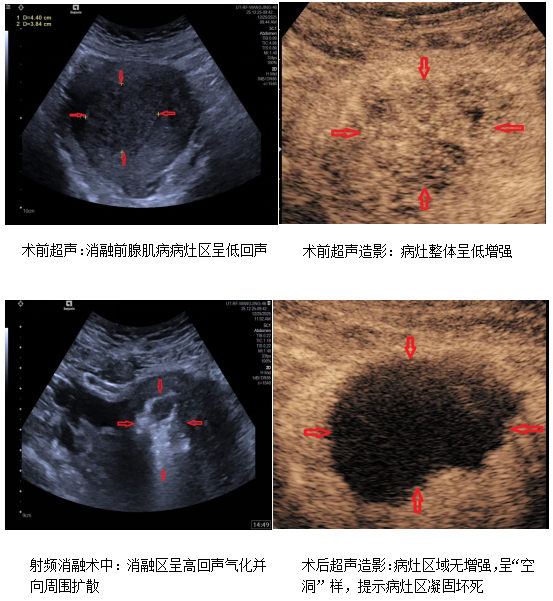

术中通过超声引导下人工腹水注入,隔离子宫与盆腔其他重要脏器和组织,有效保护包括肠管及膀胱等盆腔脏器免受无辜热损伤。在实时超声精准导航下,射频消融电极针分层分次穿刺进入子宫病灶区域,采取多点多次叠加消融模式,顺利完成病灶区消融操作,术前超声造影显示病灶区域血供丰富,呈“低增强”,术后即刻超声造影消融病灶区无造影剂灌注,呈无增强“空洞”样表现,客观验证了消融效果,提示病灶区域凝固坏死,消融成功。术后两位患者无并发症及特殊不适,24小时内顺利出院。此次微创手术不仅成功避免了传统子宫切除,保留女性生殖器官的完整性,减少了子宫切除术后的各种后续问题,同时有效改善和解决患者痛经症状,待术后治疗区域逐步回缩修复,亦可改善由于子宫肿大压迫周围脏器引起的便秘及尿频等症状。